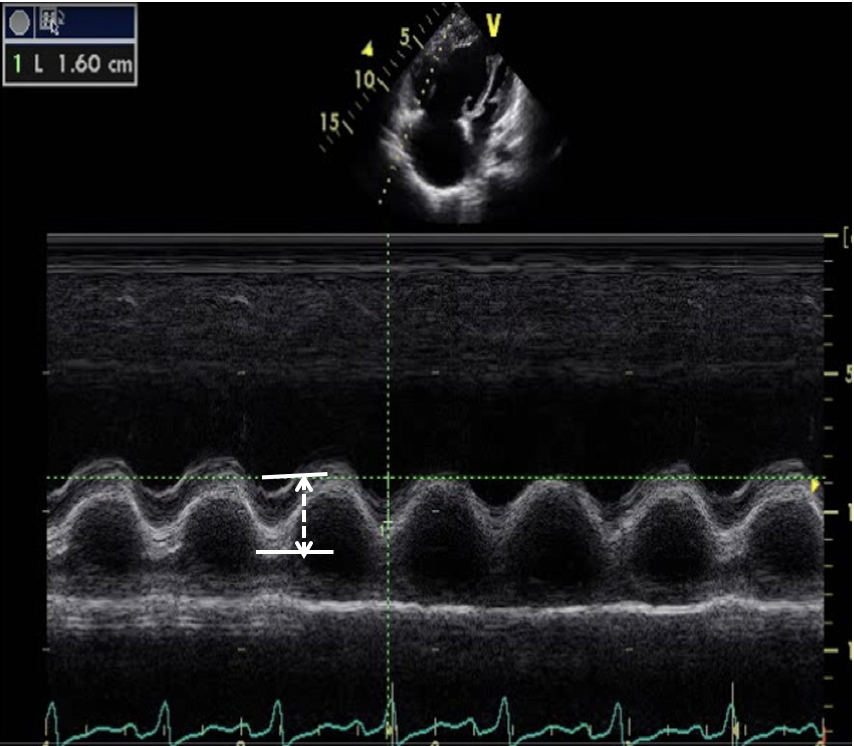

— 其他支持征象包括RV/LV基部内径>1、室间隔变平或左移、PA内径>25 mm、下腔静脉内径>21 mm及吸气时塌陷率<50%等

▲ 右心功能评估:通过右房大小、三尖瓣环收缩期位移(TAPSE)、Tei指数以及有无心包积液等间接评价

▲ 超声心动图是疑诊肺高血压时一线无创诊断方法(Ⅰ,C)